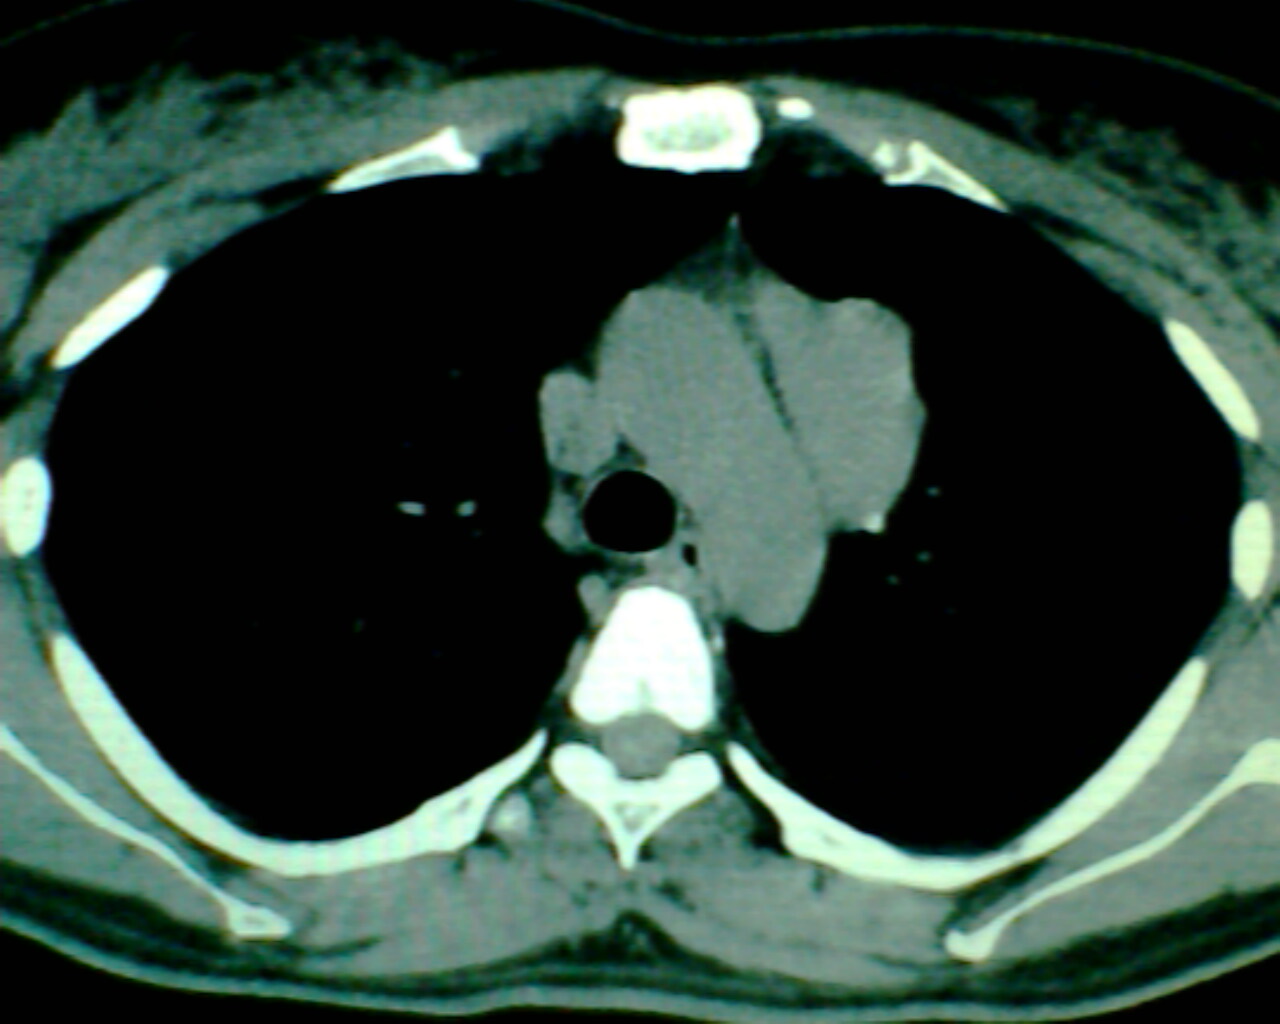

以下是引用狙击手在2007-4-10 22:46:00的发言:[br]考虑:左上纵膈旁型肺癌。理由:1,肿块与纵隔间有分隔;2,肿块呈分叶状;3,肿块突出面圆心在肺内;4,纵隔左移;5,纵隔内器官未见受压征象。